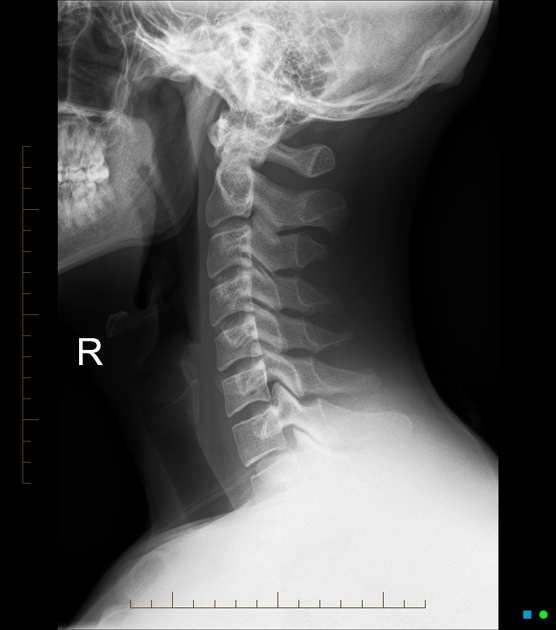

- 사무직 직장인 A씨: 하루 10시간 컴퓨터 업무 후 뇌검사에서는 이상 없음. 그러나 X-ray상 C커브 소실로 진단 → 물리치료와 운동 후 호전.

- 정확한 진단: MRI·X-ray로 목 구조 확인, 필요시 신경차단술